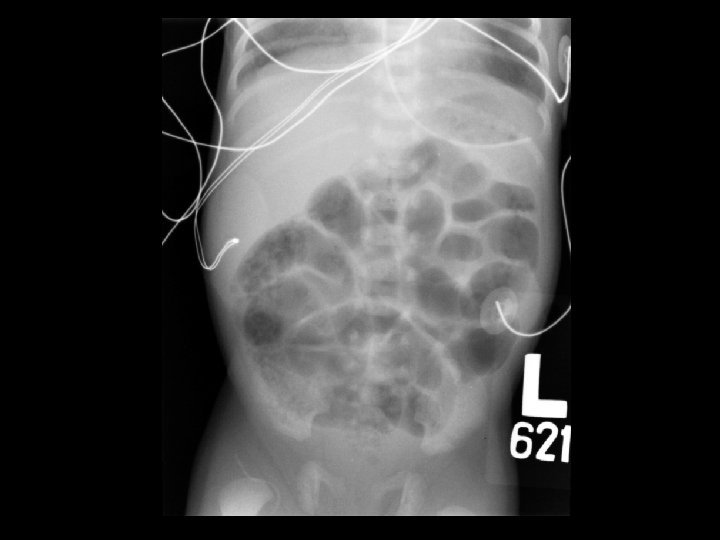

Early necrotizing enterocolitis • Findings: – Mildly distended bowel loops with “soap bubble” appearance in the RLQ – No evidence of pneumatosis or perforation • Rx: bowel rest; surgery if free gas • ddx: – NONE! – This is an Aunt Minnie!